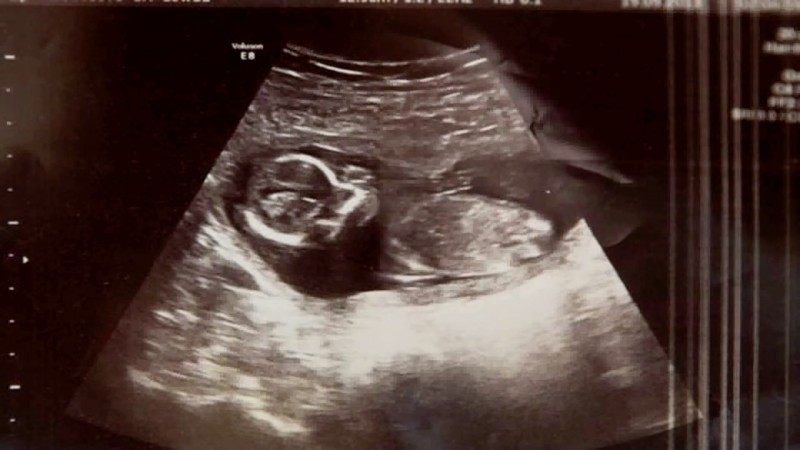

Los médicos del Hospital Rotunda, en Dublín, le hacen una ecografía a Michelle una última vez antes del legrado y, entonces, ¡oyen el inconfundible latido de un corazón! Pese al aborto, Michelle sigue embarazada. Resulta que estaba embarazada de gemelos, pero perdió a uno en el aborto. ¡Cómo pudo sobrevivir el otro bebé es algo que ni los médicos pueden explicar!

«El médico salió y volvió de nuevo con un colega con más experiencia, el cual repitió la ecografía y entonces le dijo a la pareja: » No lo vais a creer, pero tenemos el latido de un corazón». «Fue la mejor sensación de mi vida», cuenta Michelle. Al final, la pequeña Megan llegó sana y salva al mundo, dejando atónitos a padres y médicos por igual.

No se sabe si alguna vez se ha dado un caso como el de Megan. Hoy la pequeña tiene 18 meses y está completamente sana. Sus padres no caben en sí de gozo; así como los hermanitos de la niña, Ma (4) and Noah (2). Tampoco se sabe cómo a los médicos se les pasó por alto el otro bebé en previas revisiones. Los médicos dicen que Megan estaba escondida tras sangre y otros fluidos en la ecografía.